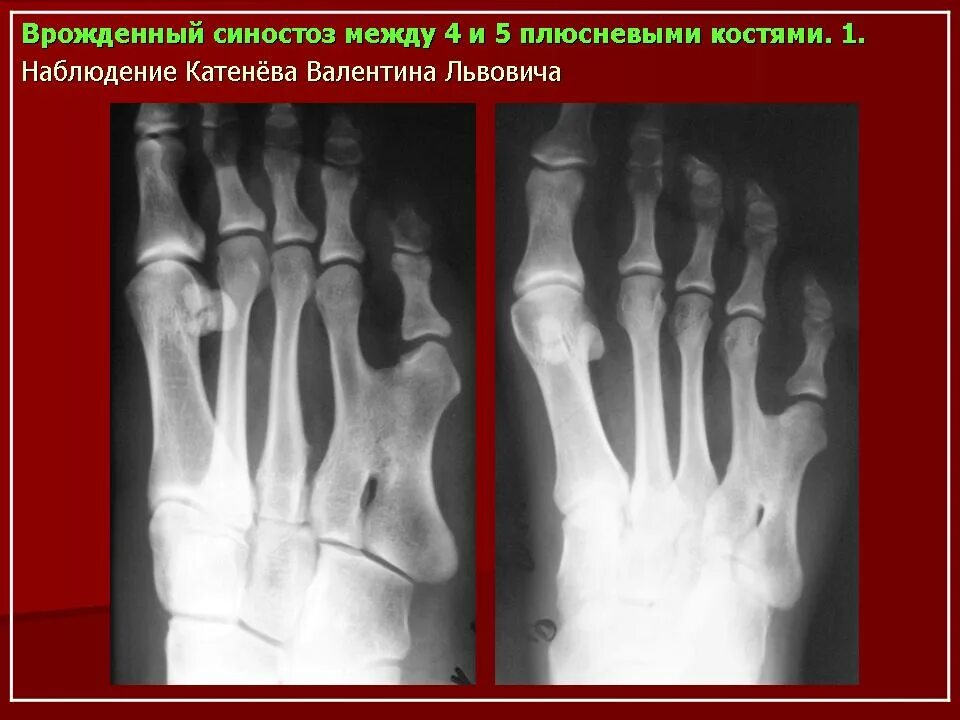

Аномалии костей